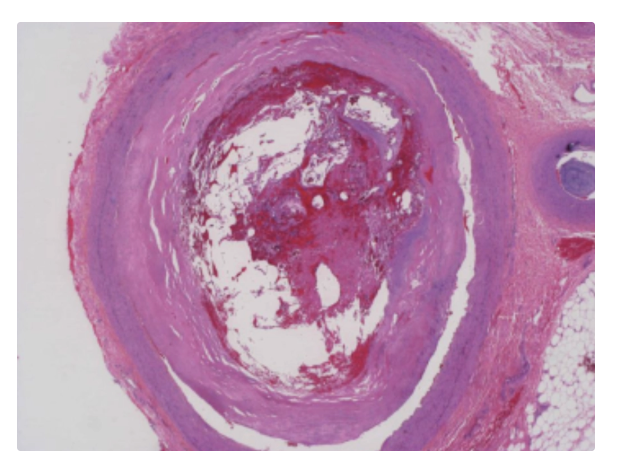

dark red recent coronary thrombosis